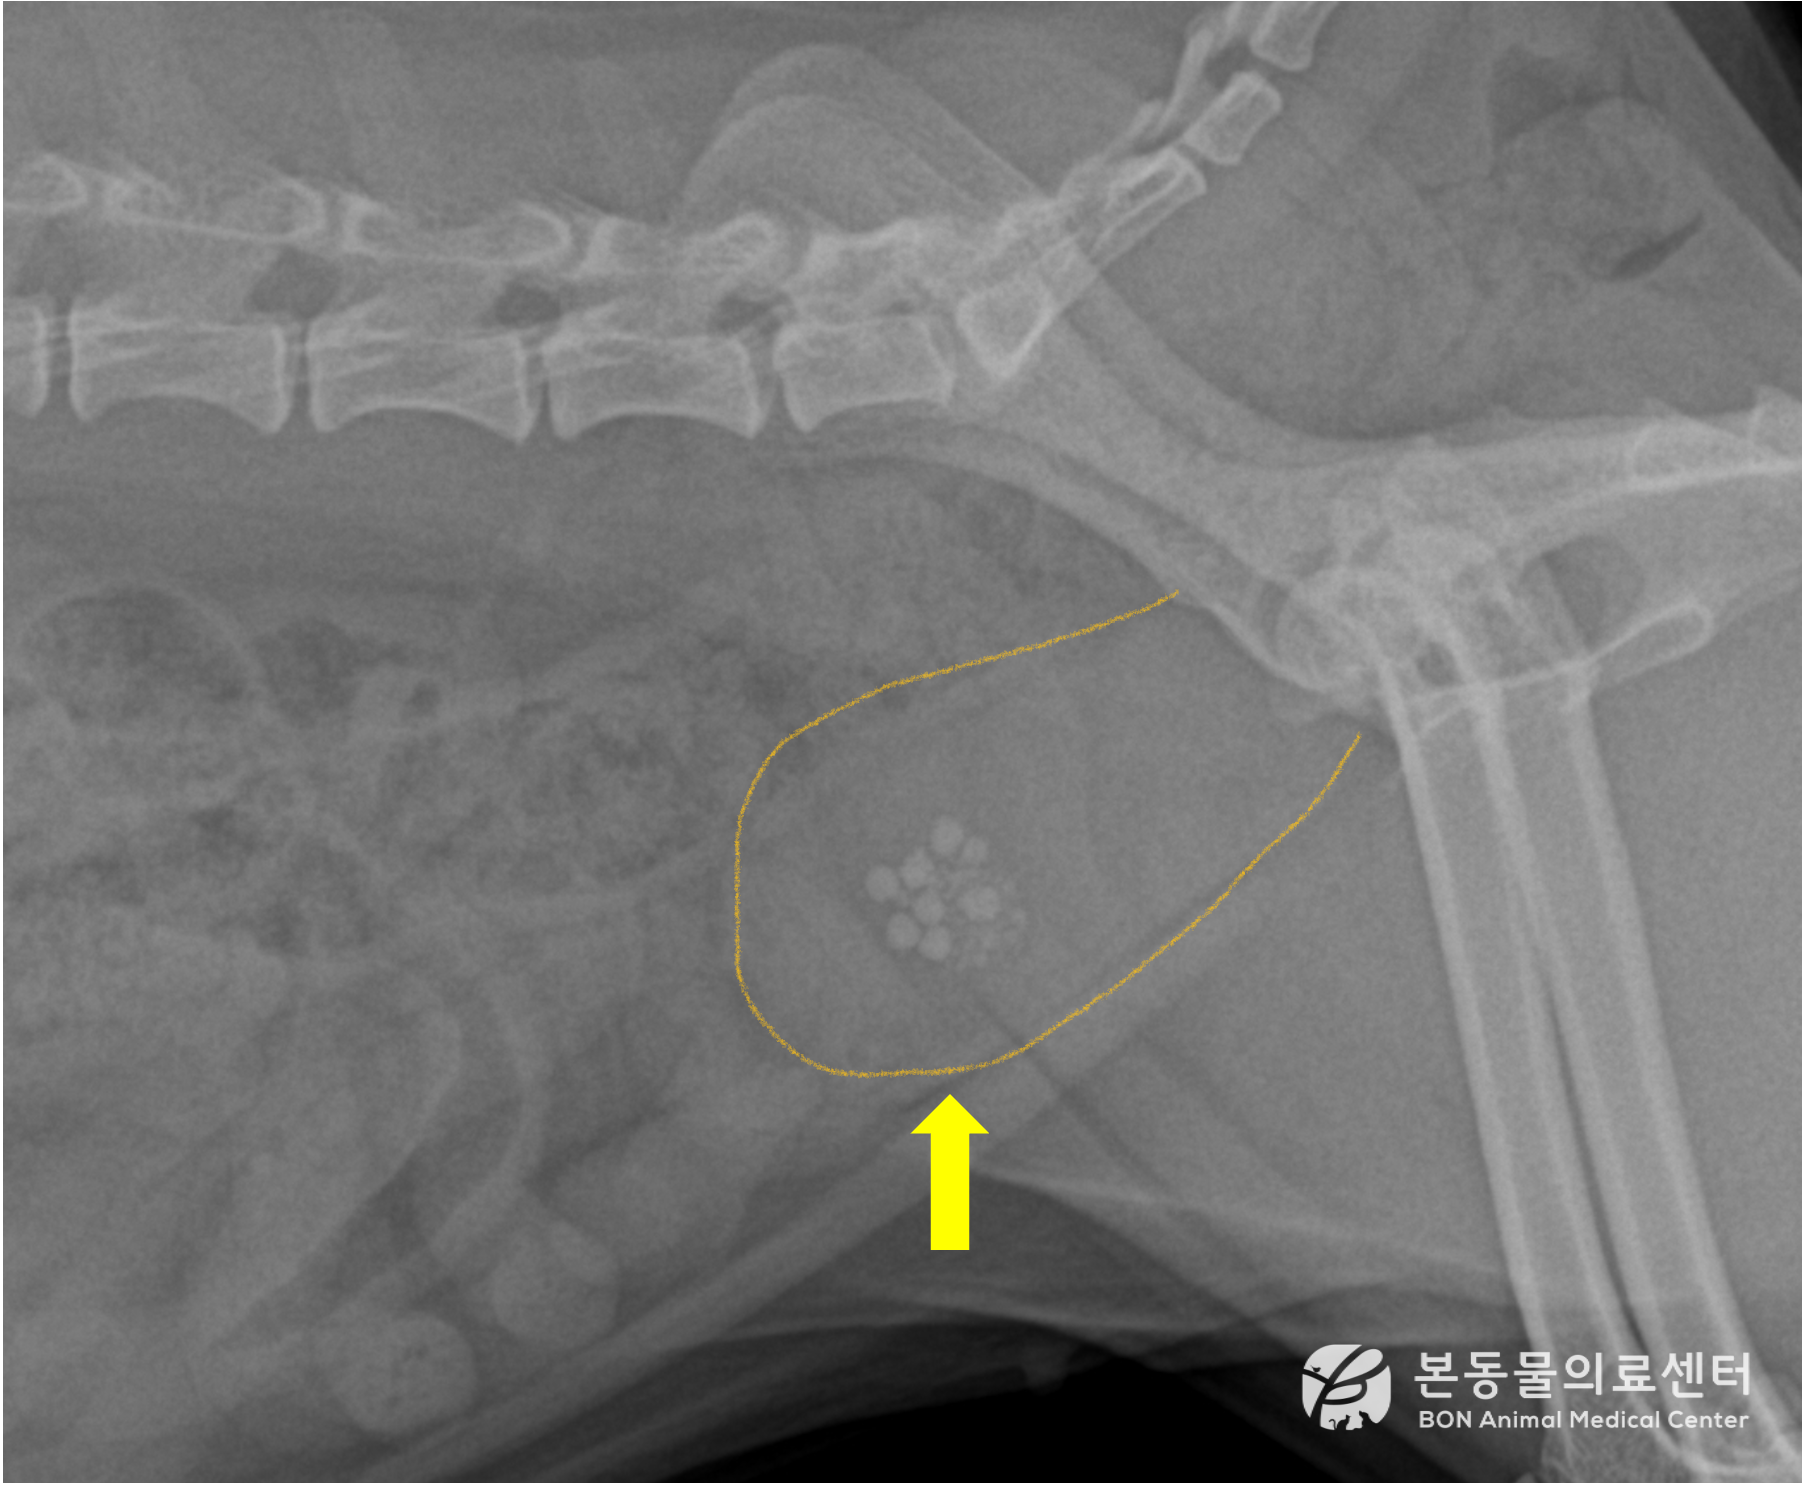

레이저 파쇄술 전 후 비교

<수술 전>